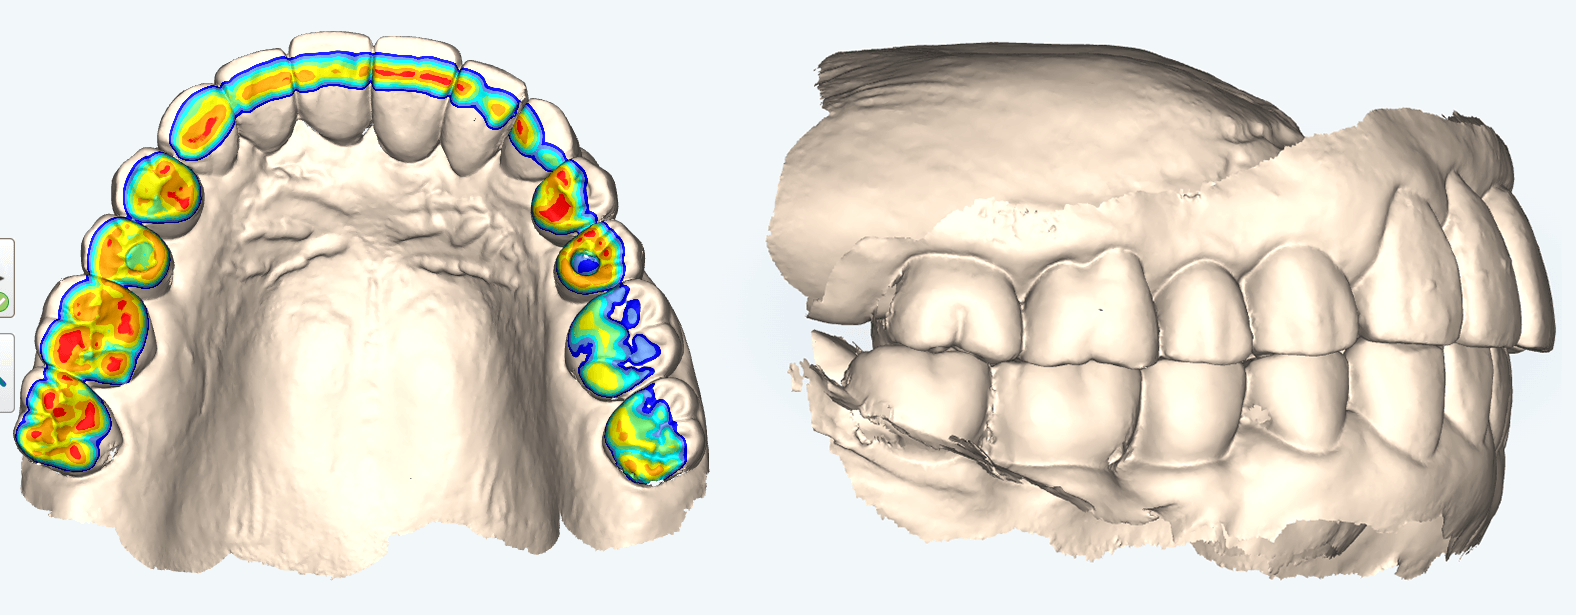

当院では、体の歪みを調べ、その方にとって無理のない安定した顎位を見つけ出し、その位置で噛み合わせを構築することを重要視した矯正治療を行っています。

また、歯列矯正だけではなく、全顎的に歯の治療(補綴治療)を必要とする方も体の歪みをみる上で治療をすることがとても重要です。